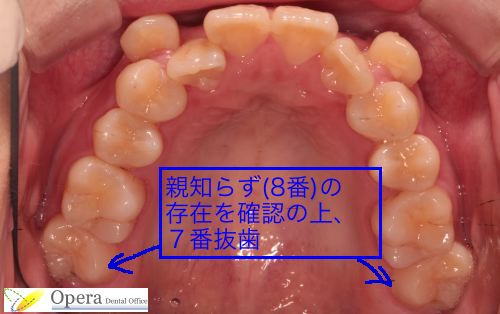

ただし、歯を抜かないわけではありません。親知らず(8番)は抜歯します。また、上顎に関しては第二大臼歯(7番)を抜きます。

「えっ?大臼歯を抜くの?」と思われるかもしれません。しかし大丈夫です。親知らずが20歳頃に生えてきて、あたかも親知らずを抜いたかのような歯並びが完成します。

この患者さんには親知らずが上下左右4本ありました。

もし、小臼歯を抜歯して矯正すると

1ブロックにつき前歯2本・犬歯1本・小臼歯1本・大臼歯3本

という、バランスが悪くなることが懸念されました。

そこで4番(第1小臼歯)を抜歯するのではなく、7番を抜歯しました。

20歳頃、8番が7番の位置に生えてきて、あたかも親知らずを抜歯したかのような歯並びとして完成するからです。

上あごは奥歯が左右1本ずつ足りません。

しかし20歳頃親知らずが生えてきて、歯並びが完成します。